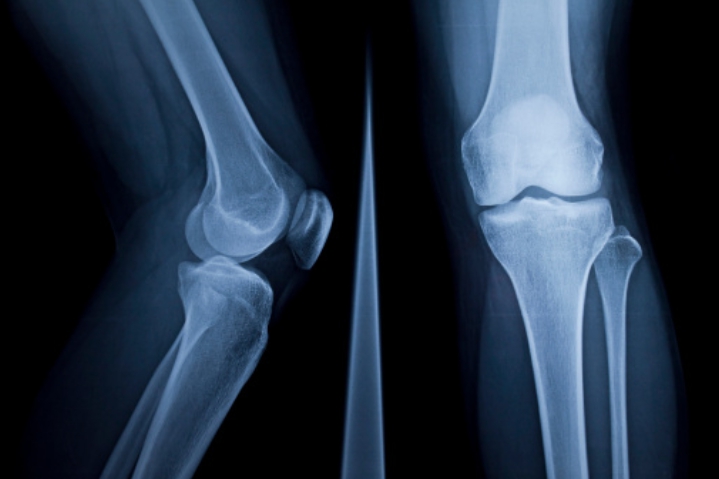

연골이 마모되면 뼈와 뼈 사이가 좁아져 관절염이 발생하여 통증이 생깁니다. 이때 콘드로이친을 복용하면 관절염 개선에 도움이 됩니다.

콘드로이친은 마모되어 얇고 연약해진 연골의 내마모성과 볼륨 유지를 개선하여주는 역할을 합니다. 연골을 보호하고 염증이 생긴 관절에 쿠션을 제공하여 통증을 완화시키고 일상생활을 원활하게 하도록 하는데 도움이 됩니다.

콘드로이친은 연골 손상을 막을 뿐만 아니라 손상된 연골의 주요 성분인 연골세포를 재생시켜 연골 기능을 향상해 주는 역할을 합니다. 연골 손상으로 고통을 호소하는 사람들에게 도움이 됩니다.